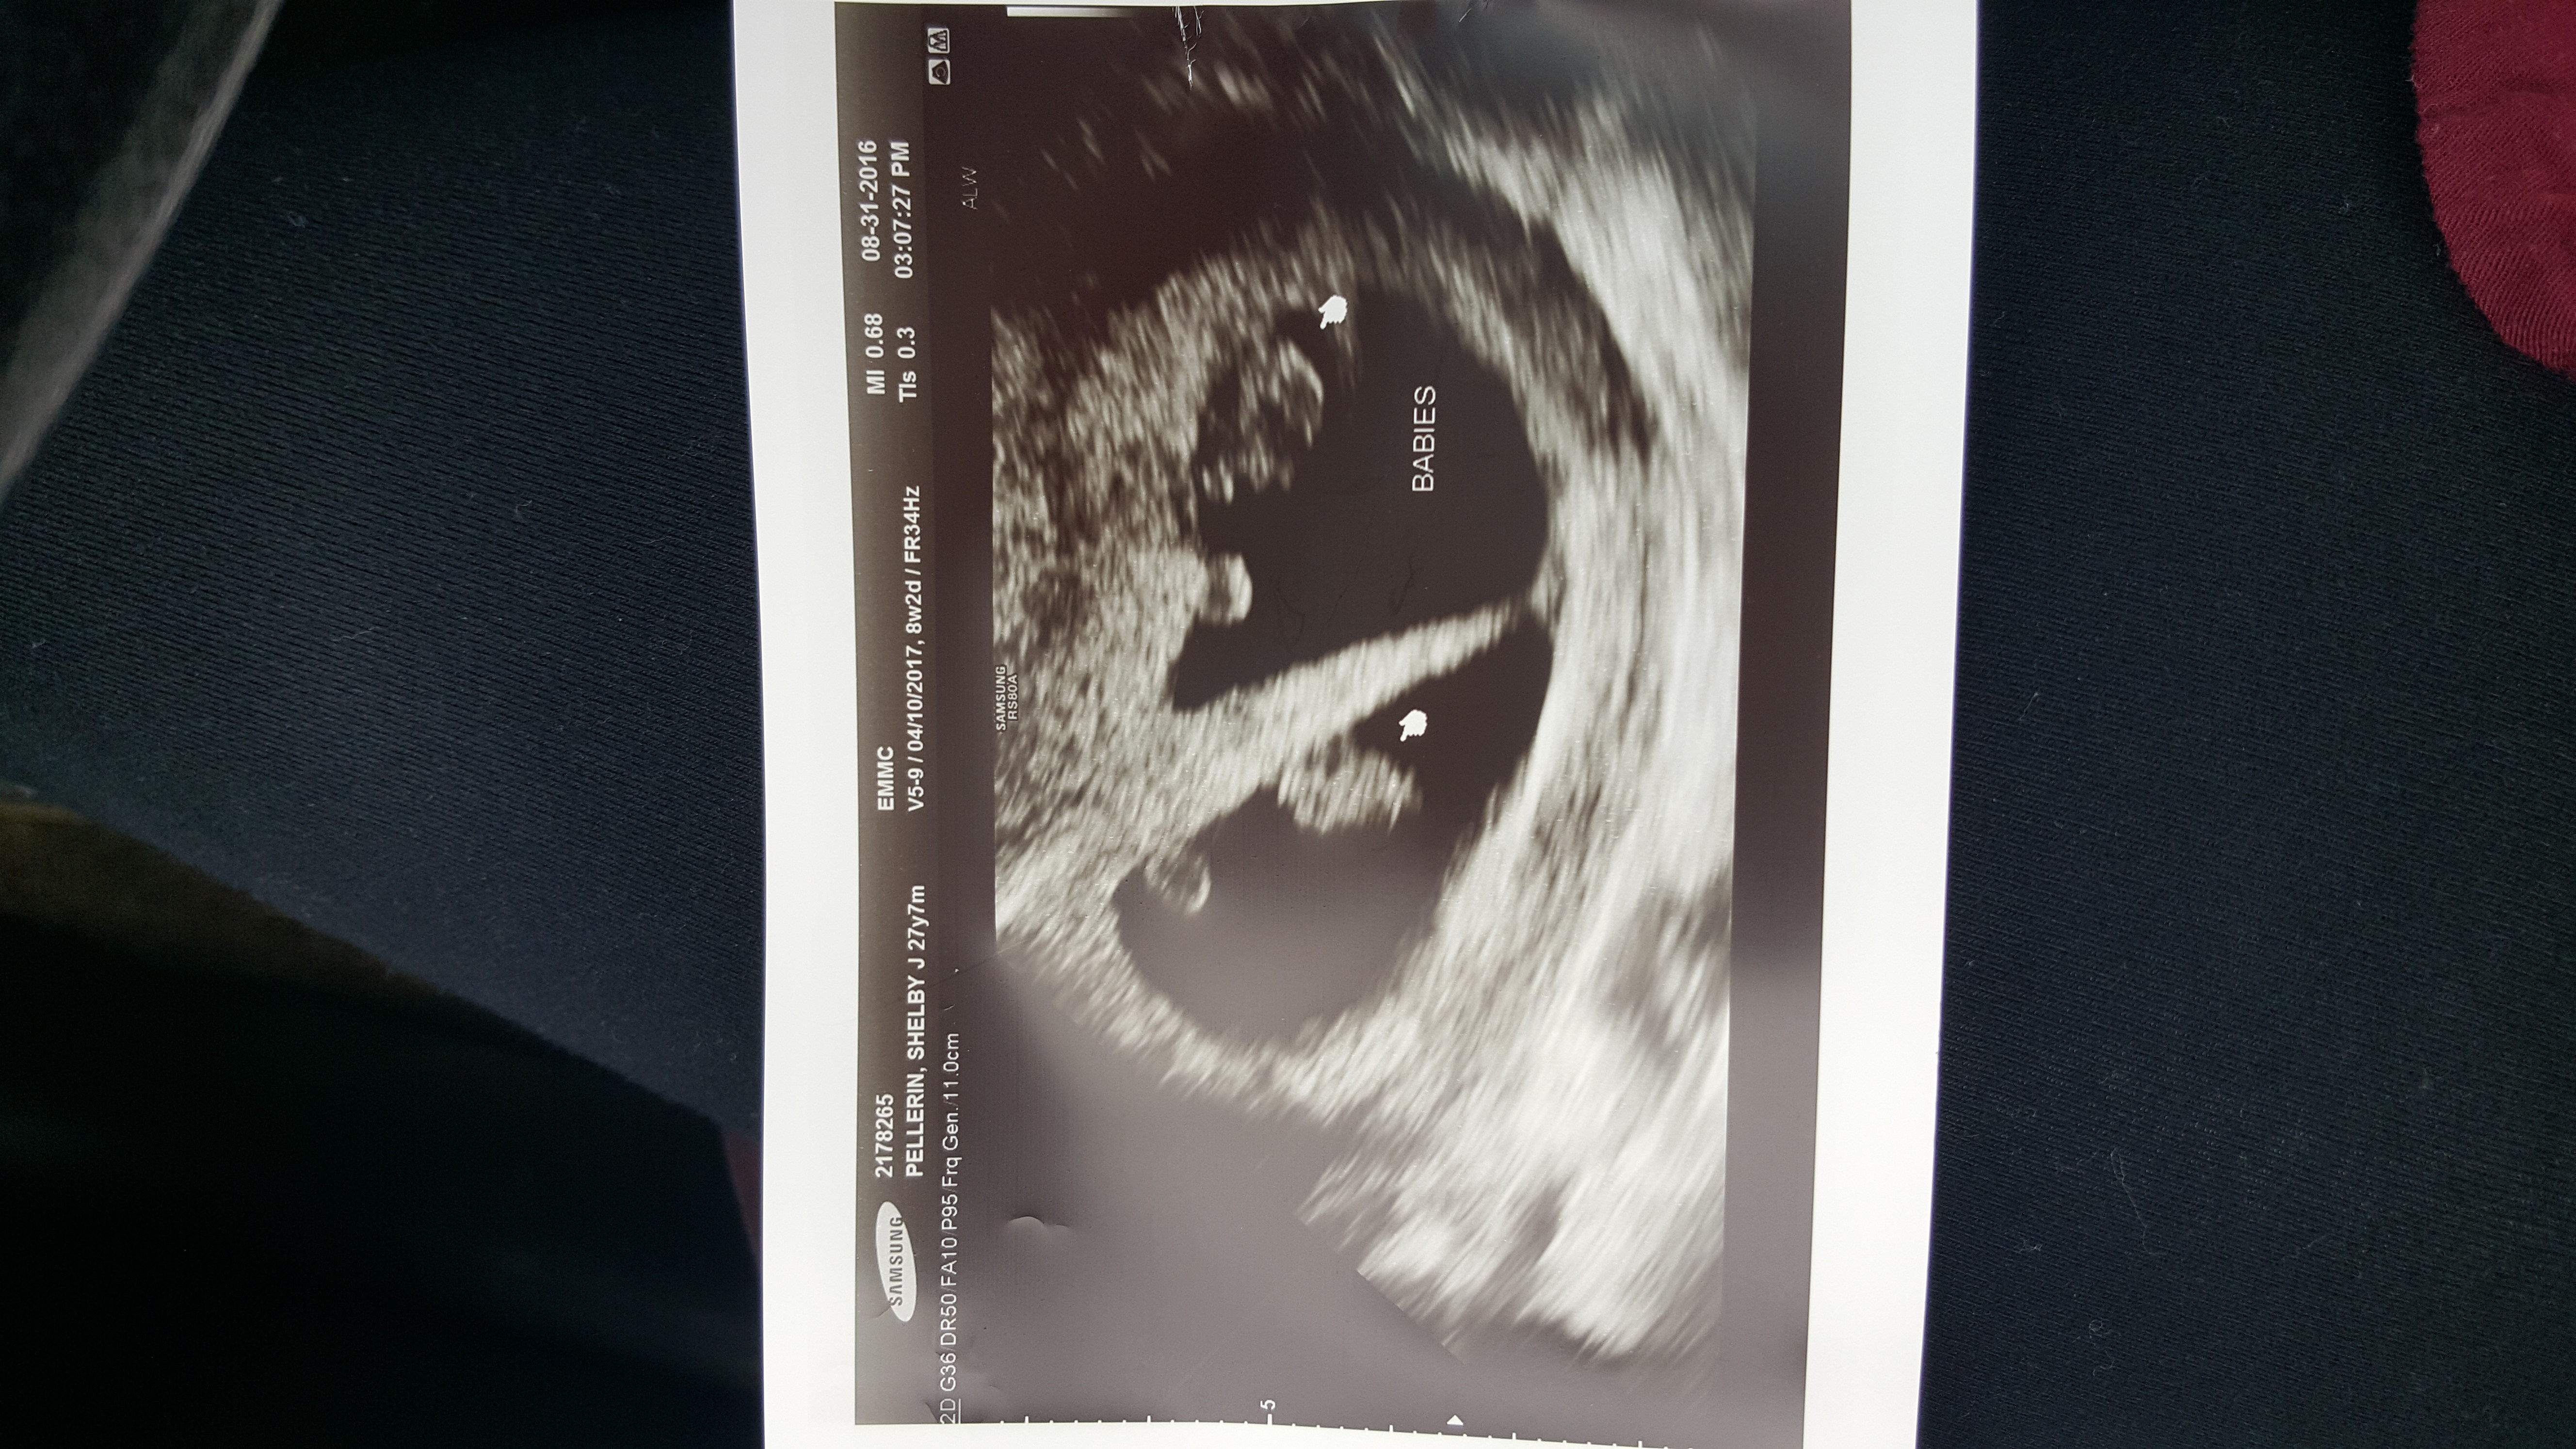

Almost 5 tears ago I lost my baby. I was only 3 1/2 months along. Then again earlier this year on May 11th my husband and I lost another baby. We were heartbroken since we had been trying for a while. One Wednesday morning I got up and was getting ready for work when I just thought I should take a at home pregnancy test, I had one left from the last time. It was positive❤😊 and we was praying with all my heart that this would all work out! We had our first 6 week appointment and the Dr's confirmed that I was pregnant. We were finally gonna be the parents we had wanted to be for so long!! Our next appointment was our ultrasound. We were so excited to see our tiny miracle, but we got a surprise. The nurse told us that we were not only having one but two babies! Twins! Our boys are due April 10, 2017💙💙 We are so excited but so nervous at the same time! Now we not only need one but two of everything!!